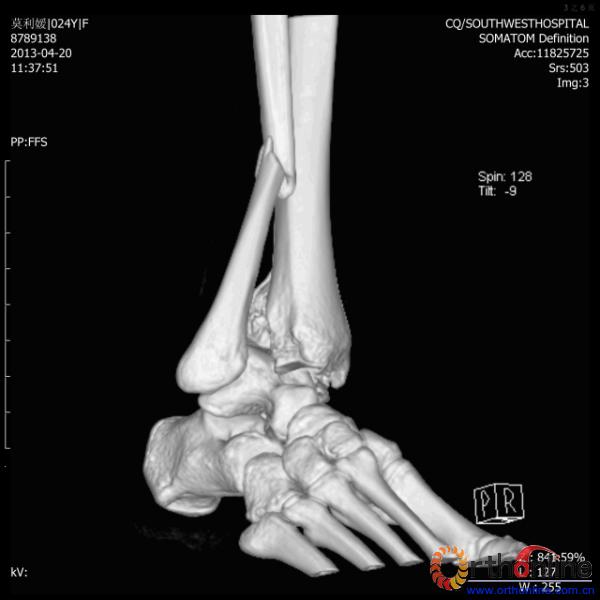

2013年4月20日 8:02分四川雅安芦山县发生7.0级地震后,重庆市有震感,24岁的莫老师在赶往上班的途中突遇此事,导致右踝关节畸形,不能站立和行走。

伤员和家属迅速赶到西南医院,10点关节外科段小军副教授查看伤员后急诊收入院,拍摄X片和急诊行三维CT重建检查,提示踝关节创伤严重,出现三踝骨折伴胫距关节脱位,需要急诊手术治疗。随后段教授与正在四川成都参加“汶川地震5周年灾害医学救治研讨会”的杨柳主任联系,进一步完善救治方案。地震当晚,段教授为该伤员进行急诊手术,手术顺利对复杂骨折进行了解剖复位,有效的钢板螺钉固定。术后伤员的疼痛明显缓解,复查X片,踝关节结构恢复满意。

患者术前CT(一)